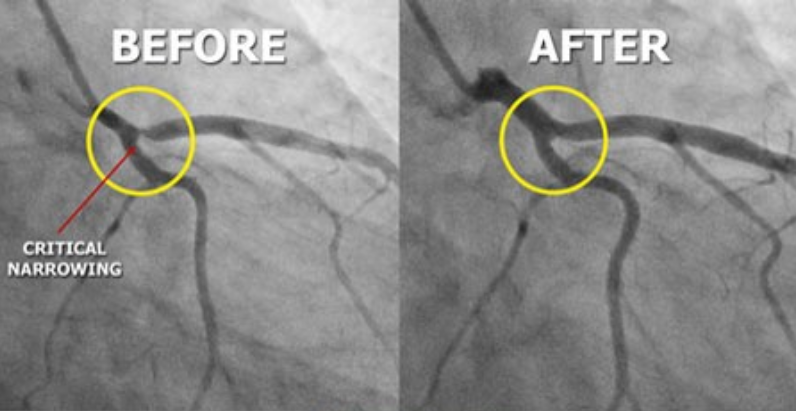

지금까지 혈관 재생을 목표로 한 치료법에는 줄기세포를 이용한 접근법이 있다. 혈관 재생을 위한 임상시험은 1997년 아사하라의 혈관내피세포 발견 이후 시작되었으며, 최근에 이르러 임상시험이 활발해지고 있다.

막힌 혈관을 뚫어주고 막힌 혈관 주위에

우회 혈관을 만들어 혈류량을 증가시킴